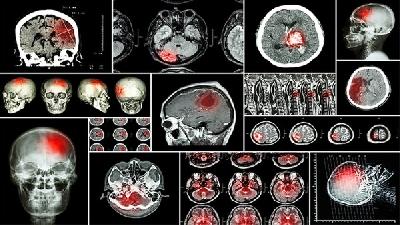

对于脑瘫的遗传问题,很多的患者及家属都有自己的担心。脑瘫治疗医院专家指出:脑瘫是由于新生儿脑组织缺血、缺氧因素引起脑损害疾病。因其具有特殊性,加上其致病因素比较多,一定程度上会对脑瘫的遗传造成不可逆的影响。

脑瘫可能由产前缺氧、早产低体重、新生儿黄疸、遗传代谢异常等原因引起,症状表现为运动障碍、肌张力异常等,需通过康复...